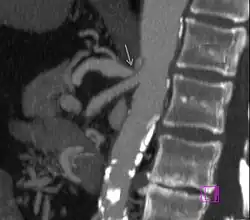

| CT-angiographische Befunde beim Truncus-coeliacus-Kompressionssyndrom[1] |

- Diagnostik: früher erfolgte zur Sicherung der Diagnose eine Angiographie, welche heute durch eine CT-Angiographie oder MRT-Angiographie ersetzt wurde, wobei die CT-Untersuchung wegen der besseren Darstellung der benachbarten Bauchorgane bevorzugt wird.[4]

Die Befunde einer kurzstreckigen Einengung des Truncus coeliacus an seinem Abgang mit nachfolgender Erweiterung (poststenotische Dilatation), einer Einkerbung im oberen Aspekt des Truncus und eines hakenförmigen Verlaufes des Truncus unterstützen die Diagnose eines Truncus-coeliacus-Kompressionssyndroms.[1] Diese Bildkriterien sind in Exspiration betont und finden sich zum Teil sogar bei asymptomatischen Patienten, die nicht an dem Syndrom leiden.[1]

Auch müssen andere mögliche Differenzialdiagnosen bei einer abgangsnahen Einengung mit poststenotischer Dilatation, wie zum Beispiel arteriosklerotische Veränderungen, berücksichtigt werden.[1] Hier kann der hakenförmige Verlauf des Truncus coeliacus für die Unterscheidung hilfreich sein, wenn auch dieses Kriterium ebenfalls nicht pathognomonisch für das Truncus-coeliacus-Kompressionssyndrom ist. Die Häufigkeit für diese Anatomie bei normalen asymptomatischen Personen wird mit 10 bis 24 % angegeben.[1]